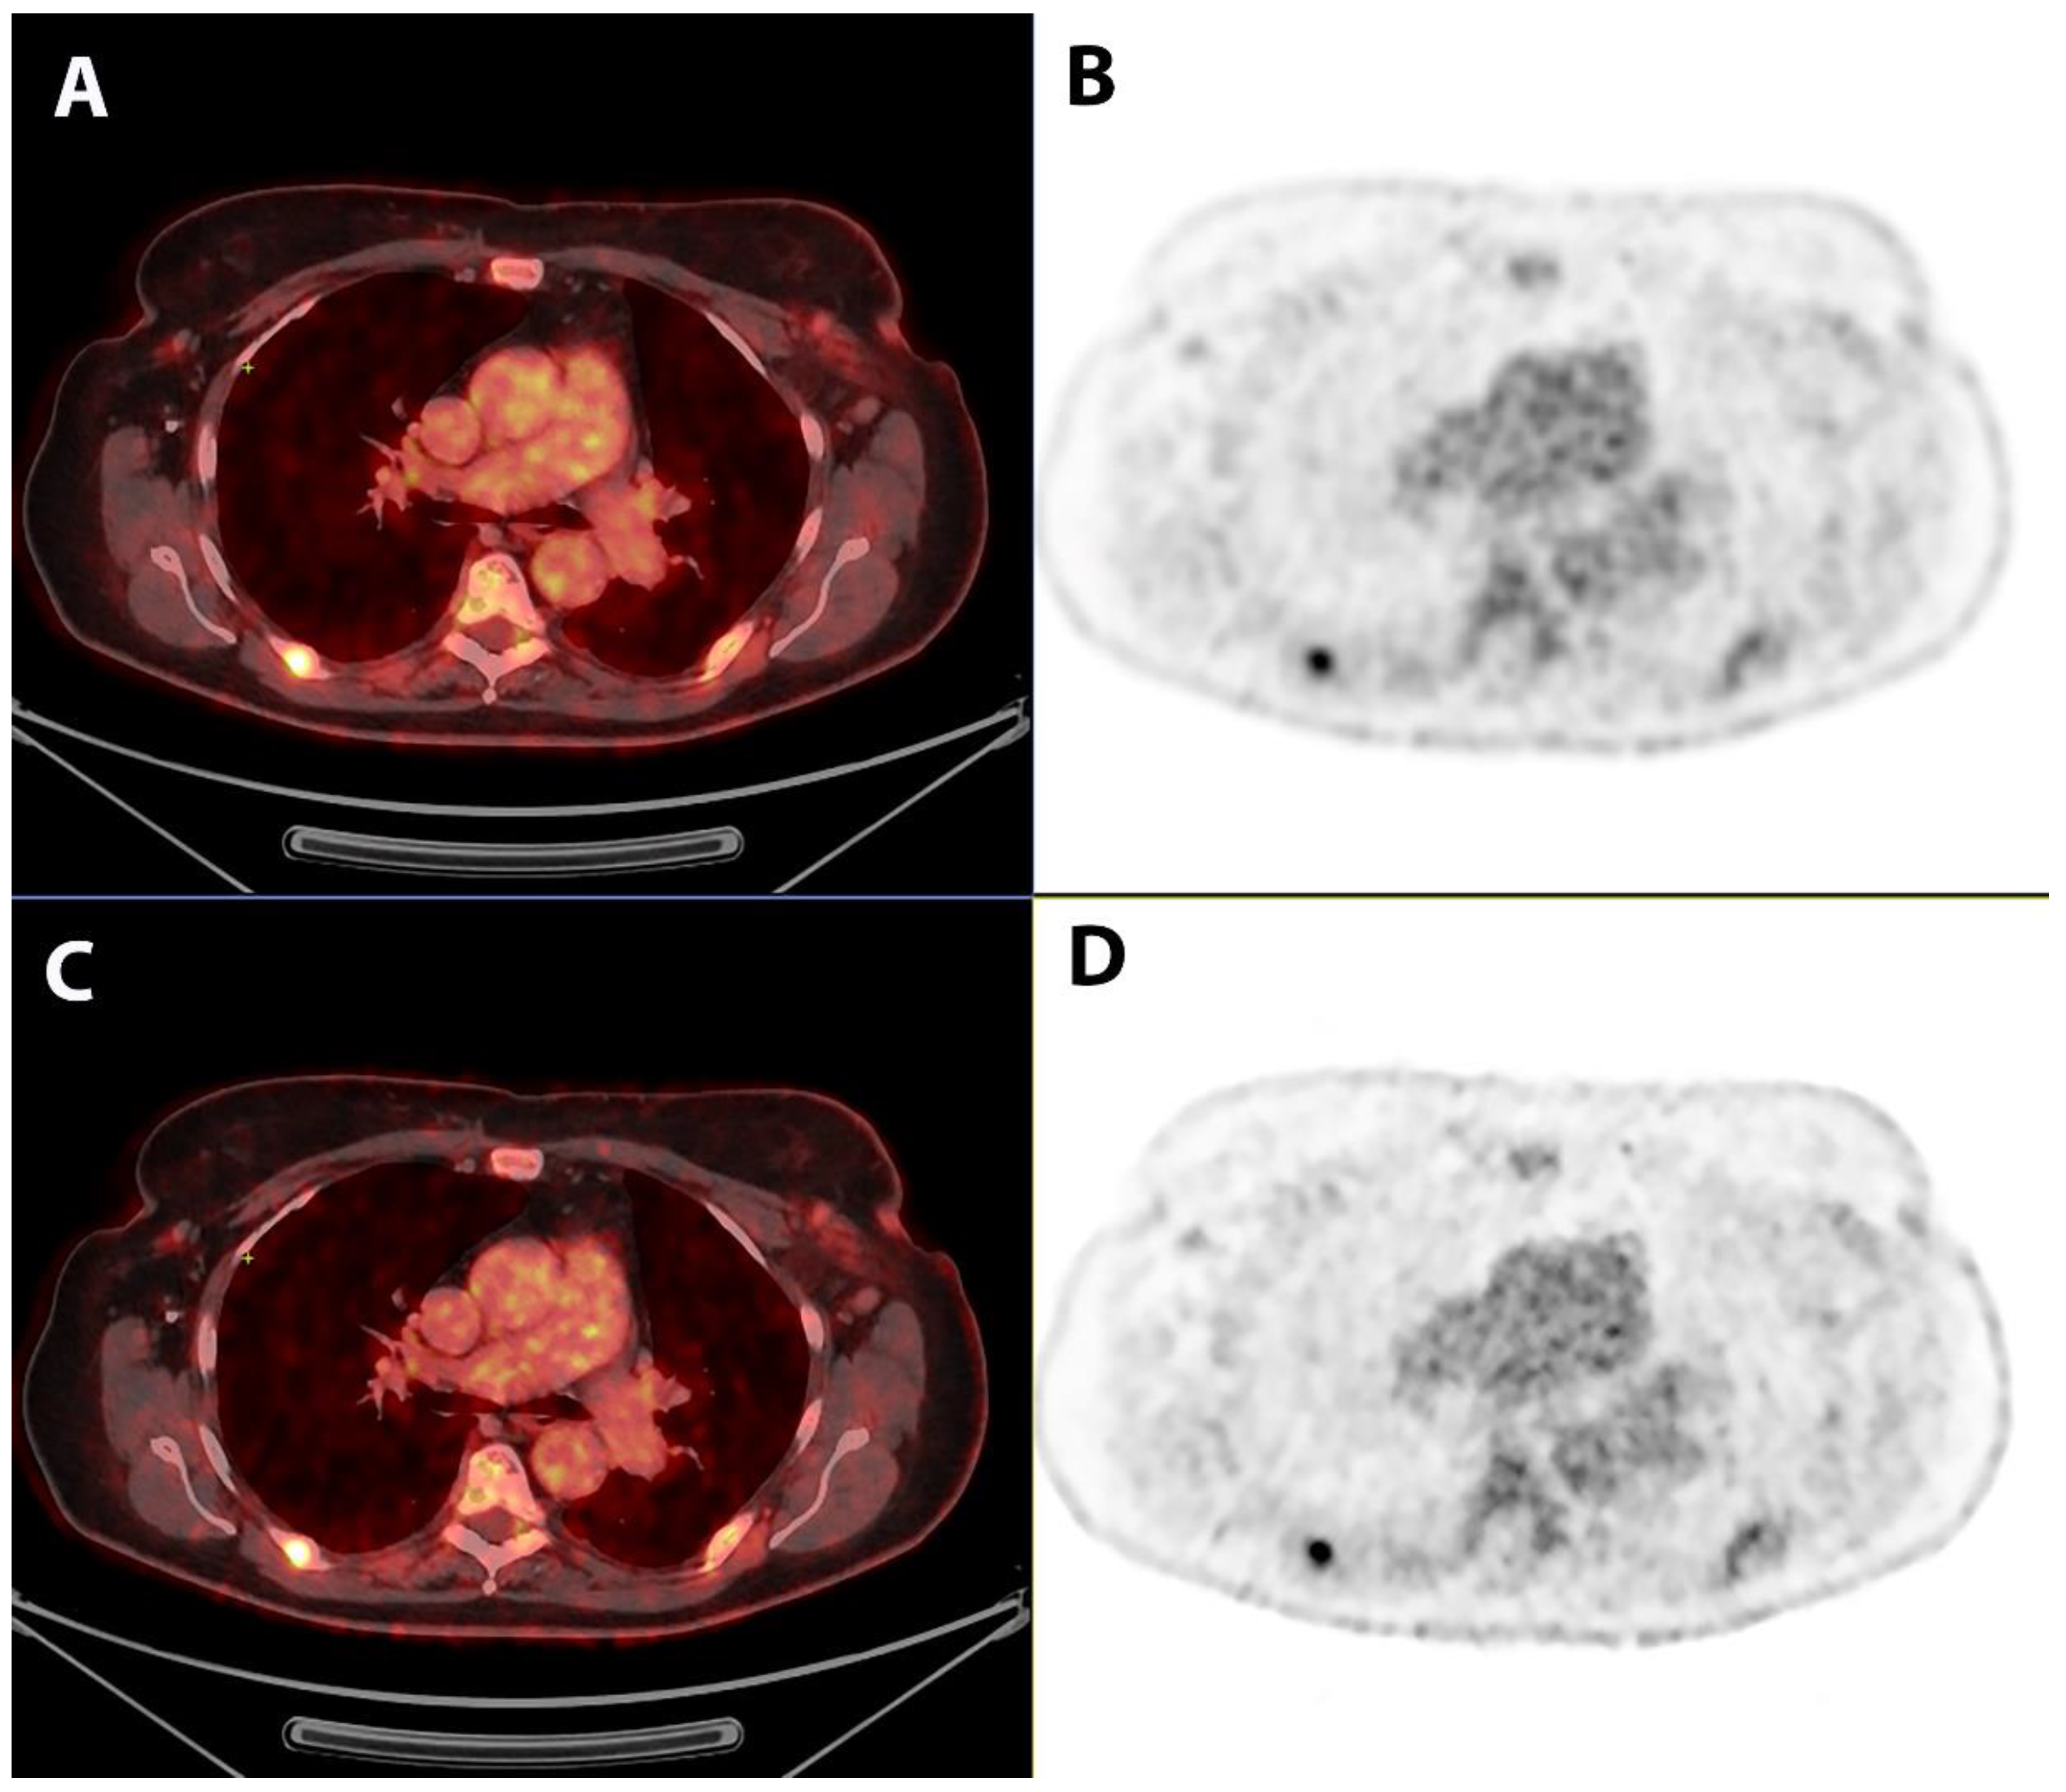

Comparison of Image Quality and Quantification Parameters between Q.Clear and OSEM Reconstruction Methods on FDG-PET/CT Images in Patients with Metastatic Breast Cancer

2.3. Qualitative Image Analysis

2.4. Quantitative Image Analysis